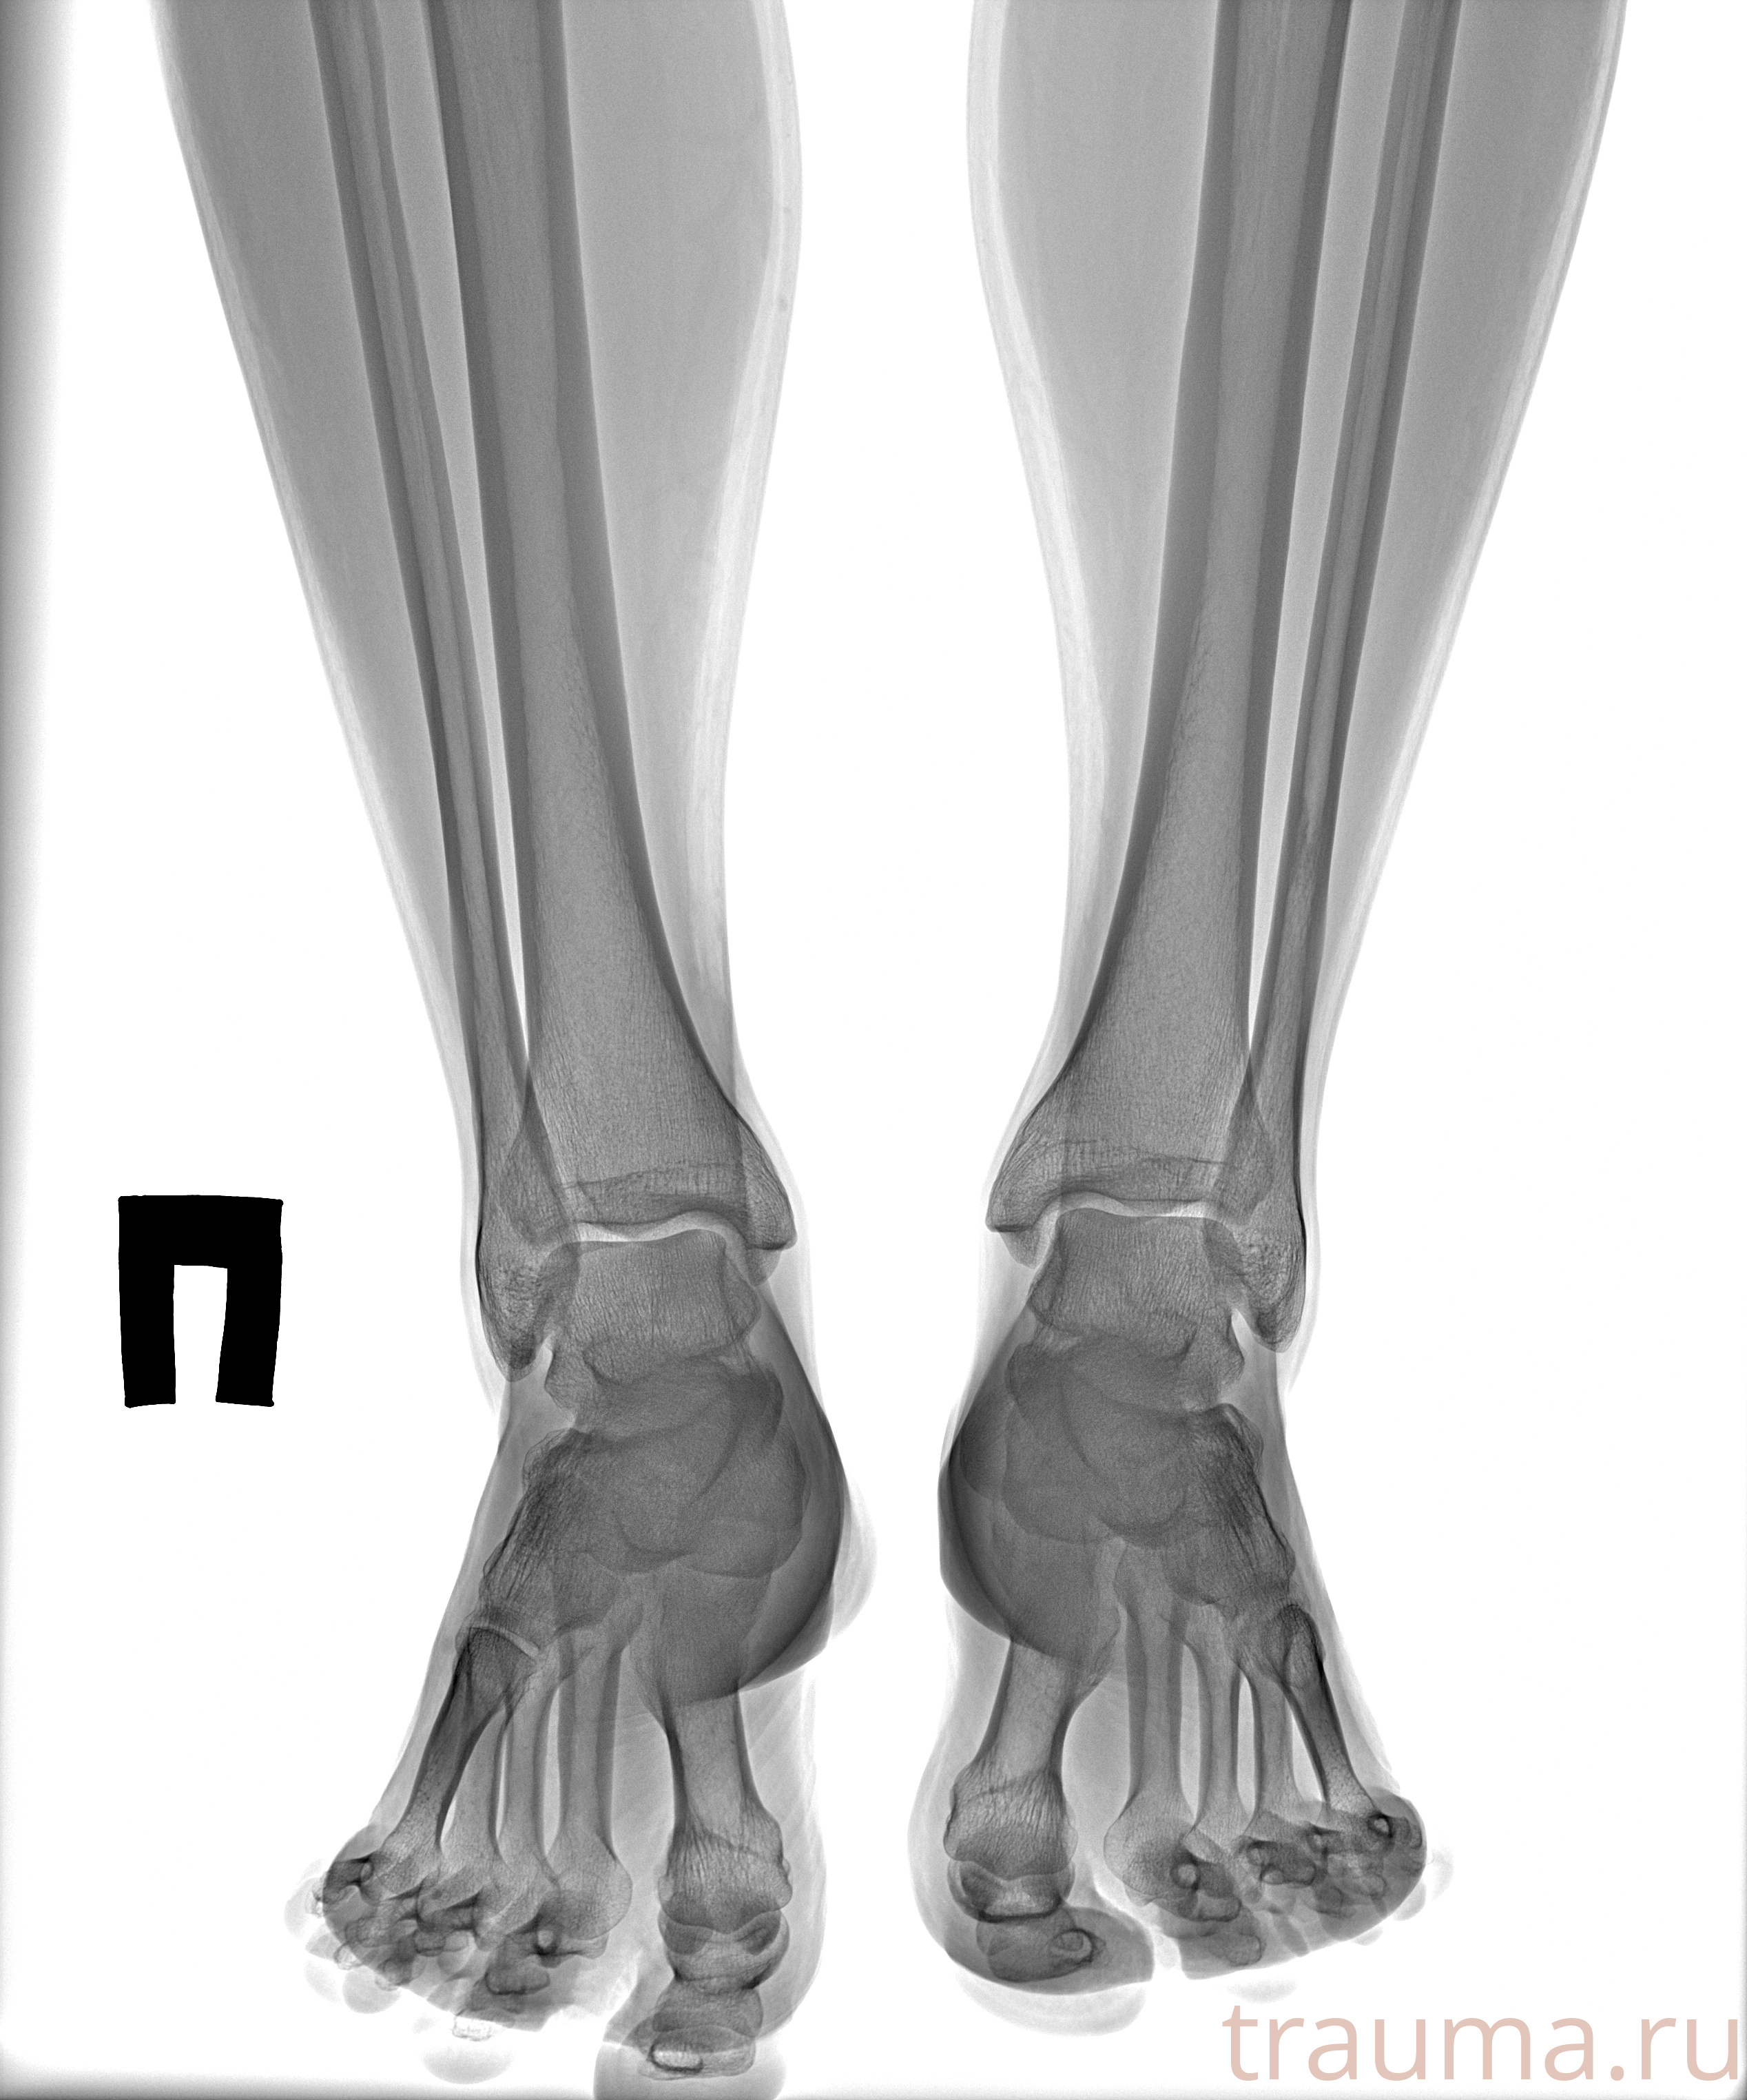

Рентгенограммы

Рентген на дому: по вашему адресу приезжает врач-рентгенолог, травматолог-ортопед с мобильным рентгеновским аппаратом, проводит диагностику травмы или заболевания, делает необходимые рентгенограммы, дает рекомендации по дальнейшему лечению. Получить качественные снимки в домашних условиях возможно благодаря уникальной методике, разработанной МосРентген Центром для института  Склифосовского